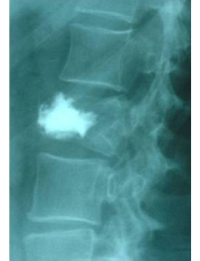

Ejemplo caso clínico cifoplastia

Comparación pre- y post-operatoria de una cifopastia cementada

Mujer, edad 55 años, Fractura aplastamiento derecho de L2

Antes 1

Después 1

Antes 2

Después 2